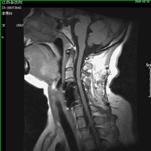

颈椎间盘突出、颈椎管狭窄——开展颈椎前路、后路手术治疗颈椎间盘突出、颈椎管狭窄,解除许多患者病痛,通过网上会诊方便患者,在家就能得到著名脊柱外科专家王少波教授诊治。

1).C4/5、C5/6间盘突出术前、 术后(C5椎体次全切除,钛笼植入)

2). C5-C6间盘突出术前、 术后(间盘切除,Cage植入)